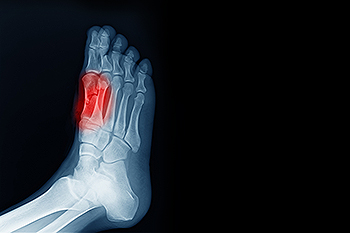

Cuboid fractures are rare and occur when the cuboid bone in the foot becomes broken. The cuboid bone is one of the smallest bones in the foot, and when it breaks, it can cause pain and trouble walking. Cuboid syndrome is a condition that is related to the cuboid bone. It happens when the cuboid bone does not move or function properly. This can cause pain on the outer part of your foot and make it hard to walk. Sometimes, cuboid syndrome can occur after a cuboid fracture because the bone may not heal correctly, or may still be out of place. If you have foot pain on the outer side of the foot, it is suggested that you schedule an appointment with a podiatrist to obtain a proper diagnosis and treatment that will help you return to normal activity as quickly as possible.

Cuboid syndrome, also known as cuboid subluxation, occurs when the joints and ligaments near the cuboid bone in the foot become torn. If you have cuboid syndrome, consult with David Mehl, DPM from New York. Our doctor will assess your condition and provide you with quality foot and ankle treatment.

Cuboid syndrome is a common cause of lateral foot pain, which is pain on the outside of the foot. The condition may happen suddenly due to an ankle sprain, or it may develop slowly overtime from repetitive tension through the bone and surrounding structures.

A common symptom of cuboid syndrome is pain along the outside of the foot which can be felt in the ankle and toes. This pain may create walking difficulties and may cause those with the condition to walk with a limp.

Diagnosis of cuboid syndrome is often difficult, and it is often misdiagnosed. X-rays, MRIs and CT scans often fail to properly show the cuboid subluxation. Although there isn’t a specific test used to diagnose cuboid syndrome, your podiatrist will usually check if pain is felt while pressing firmly on the cuboid bone of your foot.